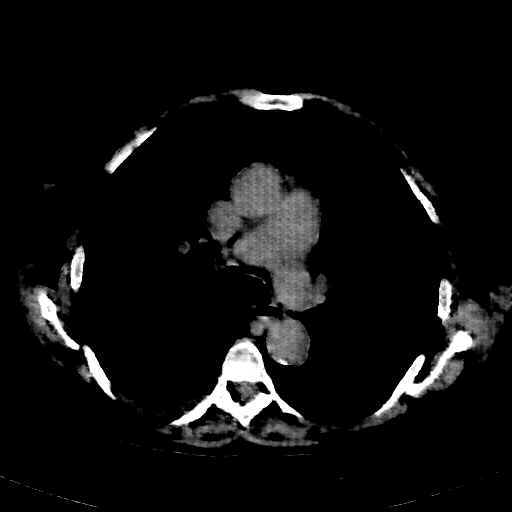

Reconstructed NATIVE CT scan (cycle consistency)

Full window (WL 1023.5, WW 4095 β†’ Low βˆ’1024, High +3071)

Actual HU range: [-1024.0, 609.2]